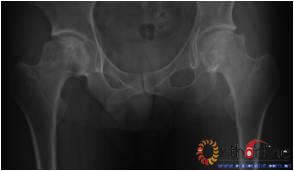

2.2 影像学结果 影像学结果与临床结果基本同步。临床结果优的36髋,34髋维持圆形且修复较完全(图1)。1例双髋Ⅲa激素性(SARS患者)ONFH,术后随访7年8月,X线片显示股骨头虽不圆,但临床HHS评分90分为优(图2)。功能为良的12髋,7髋股骨头不圆,但股骨头与髋臼匹配好,其余5髋股骨头维持圆形。临床评定为差的17髋,股骨头均有超过4mm塌陷,股骨头与髋臼匹配不好,股骨头内无折断,MRI未显示骨髓水肿,关节间隙呈不对称改变,CT扫描示软骨下骨折,MRI显示骨髓水肿。

图1 女,22岁,(1)双侧股骨头坏死右侧B型,左侧C1型;(2)打压植骨术(加入BMP2)后5年,CT显示植骨生长良好,关节功能正常(Harris评分96分);(3)术后7年关节功能维持正常,股骨头维持正常外形